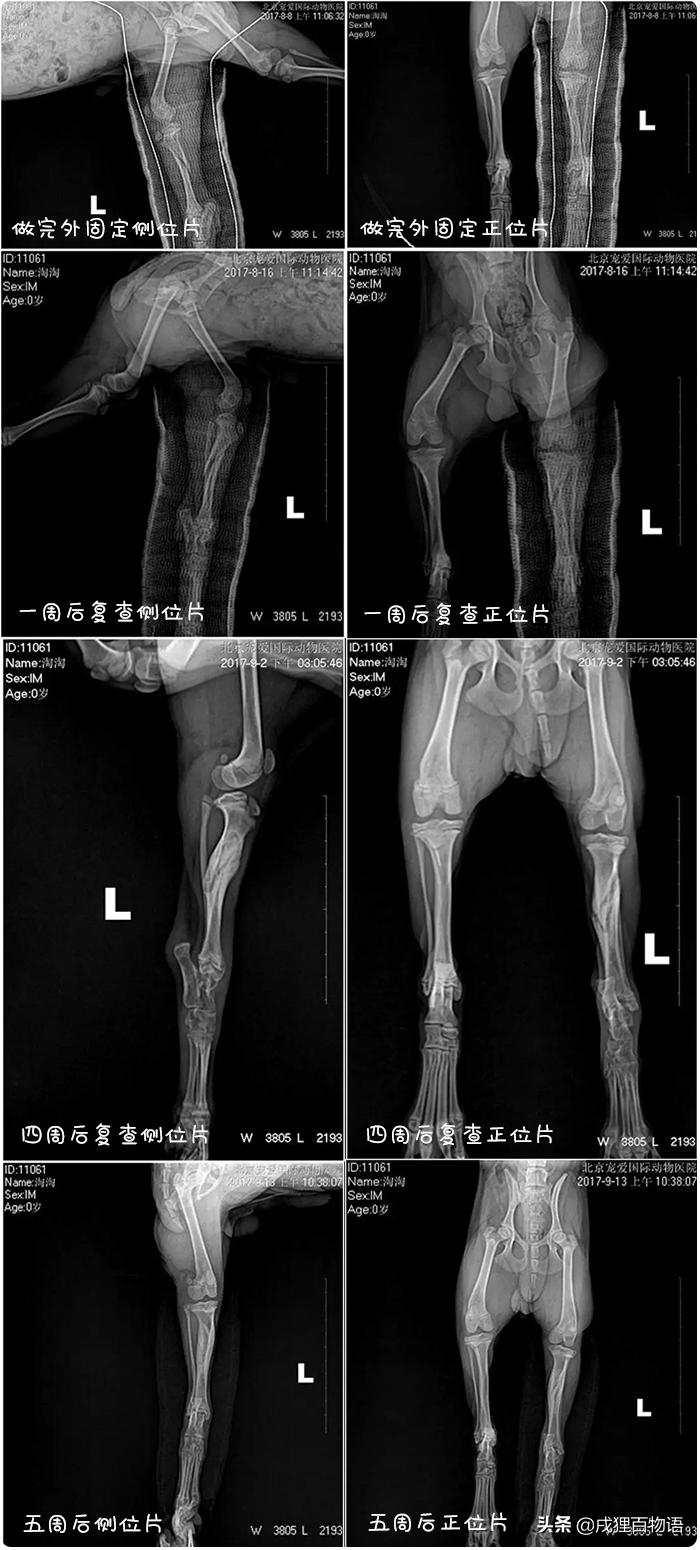

化验:DR显示左后肢不完全骨折

左后肢胫骨不完全骨折

用玻璃纤维左后肢完全缠绕骨折外固定